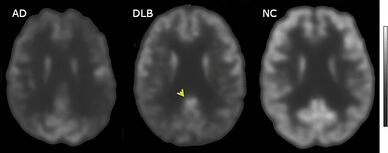

FDG-PET horizontal cross section of brain, with brighter areas indicating higher metabolism. The cingulate island sign is indicated by the arrowhead.

PET or SPECT imaging can be used to detect reduced dopamine transporter uptake and distinguish AD from DLB.[57][149] Severe atrophy of the hippocampus is more typical of AD than DLB.[150] Before dementia develops (during the mild cognitive impairment phase), MRI scans show normal hippocampal volume. After dementia develops, MRI shows more atrophy among individuals with AD, and a slower reduction in volume over time among people with DLB than those with AD.[33] Compared to people with AD, FDG-PET brain scans in people with DLB often show a cingulate island sign.[33]